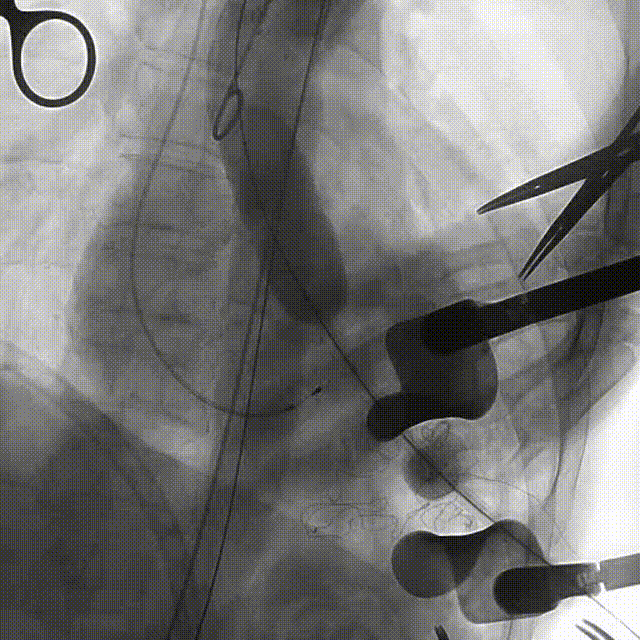

手术过程